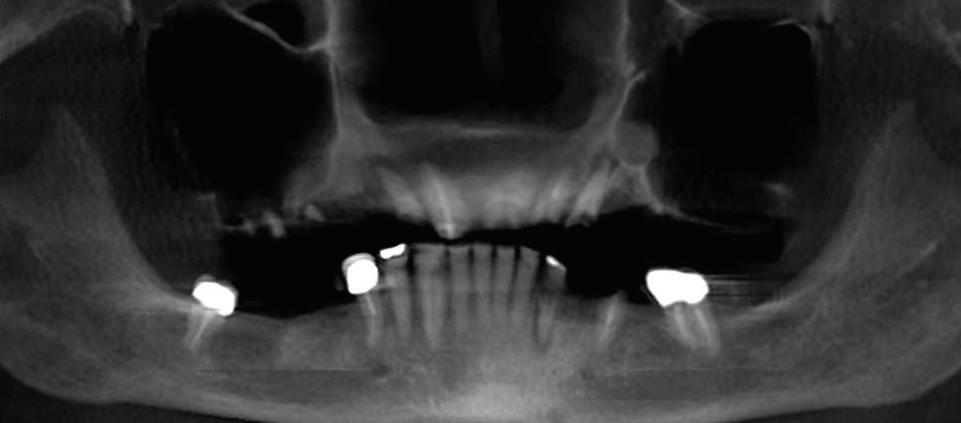

A Reason To Smile Again

Dental Implants

Can just four implants replace all of the teeth on the top or the bottom of your mouth? Thanks to advances in dental implant technology, that answer is a resounding yes.

Believe it or not, tooth loss is extremely common among adults, especially as we age. In fact, more than 35 million people in America are missing

all of their upper and/or lower teeth. Rather than living with the discomfort and hassles of dentures, many people are opting for what is called “all-onfour” dental implant restoration.

All-On-Four: One Full Arch Of Teeth, Four Dental Implants

To fully understand this remarkable technique for replacing teeth, you should first understand what a dental implant is. An implant is a small titanium screw that fits inside your jawbone and replaces the root-part of a missing tooth. Minor surgery is required to insert the implants. Once the implant is in place, a crown is attached to give you a highly realistic-looking and functional prosthetic tooth. Here’s where it gets really interesting: You do not need a dental implant for each and every one of your missing teeth. All you need is four precisely placed implants on the top of your